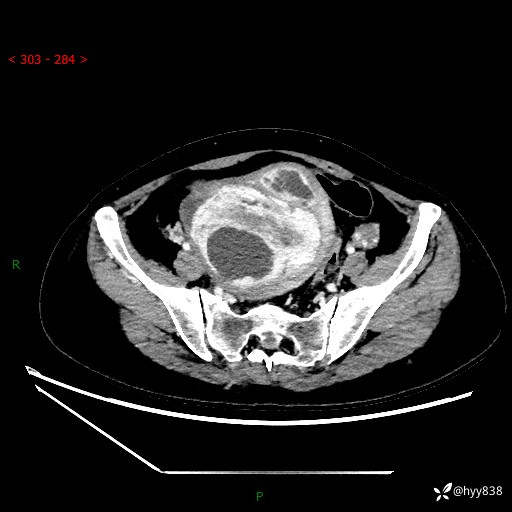

辅助检查:CT

盆腔CT平扫

增强(动脉期+静脉期)